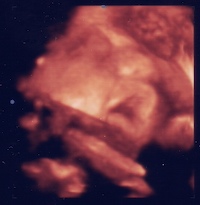

Vanoval minden rendben, dobog a kis szivecskeje, szep a fejecskeje, lattuk a kis veseit, mindene ok szerencsere, eppen szundikalt az uh alatt

de a placentam nincs jo, helyen, meg mindig csaszarnak tünik

ez meg önmagaban elfogadhato, de elmeseltem a dokinak a pecsetelgetest, es ez mar egyaltalan nem tetszett neki

azt mondta, hogy ezt a melyen tapado placenta okozhatja, mindenesetre megvizsgalt, sextilalmat kaptunk